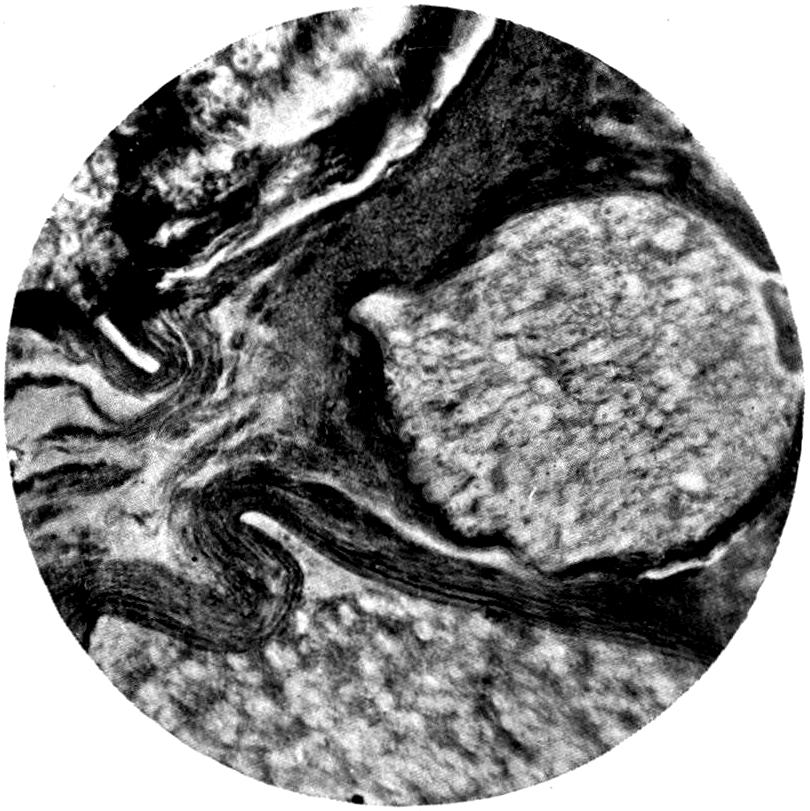

Plate I. 92

[43]

REFERENCES.

[1] Cloetta: Dixon Mann’s Forensic Medicine and Toxicology, p. 463.

[2] Oliver, Sir T.: Diseases of Occupation, p. 142.

[3] Goadby, K. W.: Departmental Committee on Lead Poisoning, etc., in China and Earthenware Manufacture, Appendix No. XXV.

[4] Meillère and Richer: Meillère’s Le Saturnisme. Paris, 1903.

[5] Blyth: Abstract of Proc. Chem. Soc., 1887-88.